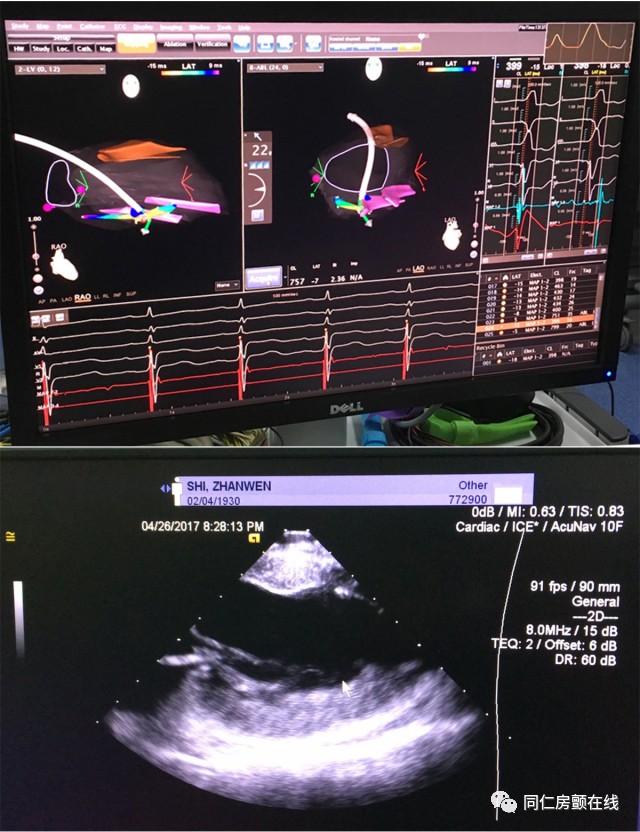

从患者心电图判断,我们怀疑这位患者的室性早搏起源于乳头肌。通俗的说,就是这种心律失常起源的部位结构复杂,消融难度相当大,手术成功率低。并且患者年龄大,还有严重的冠心病,消融治疗的风险很高。经过马长生主任、史旭波主任以及郭炜华教授的讨论,我们决定应用心腔内三维超声导管,在心腔内超声(ICE)技术的指导下为患者进行射频消融。正是得益于这项被叫做ICE的新技术,手术取得了极大的成功。

目前的射频消融,医生需要利用X线和三维标测系统,大致判断导管在心脏中的位置,而不能直接看到导管是否真正贴靠在目标结构上。心腔内超声技术(ICE)可以帮助介入医生更加直观地看到心脏里面的结构,还可以更加精确地定位消融导管的位置,为射频消融术提供了强大的指导作用。由于可以实时获知心腔内的情况,心腔内超声可以像透视一样实时指导消融的全过程,可以实时显示导管贴靠的情况,显著提高了手术的成功率;心腔内超声还能实时监测术中心腔内的变化,第一时间发现心包积液等并发症,提高了手术的安全性;此外,使用心腔内超声技术还可以有效减少X线的用量,减轻辐射对病人和医生的伤害。该项技术用于复杂性心房颤动(房颤)患者的消融治疗,不仅可以提高消融的有效性及安全性,而且还可为慢性肾功能不全、造影剂过敏的房颤患者带来福音。

CartoSound三维超声技术指导下的乳头肌起源室性早搏的射频消融

目前,心腔内三维超声技术在美国、欧洲和日本等国家的大型医学中心用于各类复杂心律失常的介入治疗。北京同仁医院血汗管中心首次将CartoSound心腔内三维超声技术用于难治性室性早搏的治疗。这次手术标志着三维心腔内超声技术这把利剑真正进入了同仁血汗管中心。今后,这项新技术将常规用于指导包括房颤在内的复杂难治性心律失常的介入治疗,将为导管消融治疗提供新的有力支持,为更多心律失常患者提供帮助!